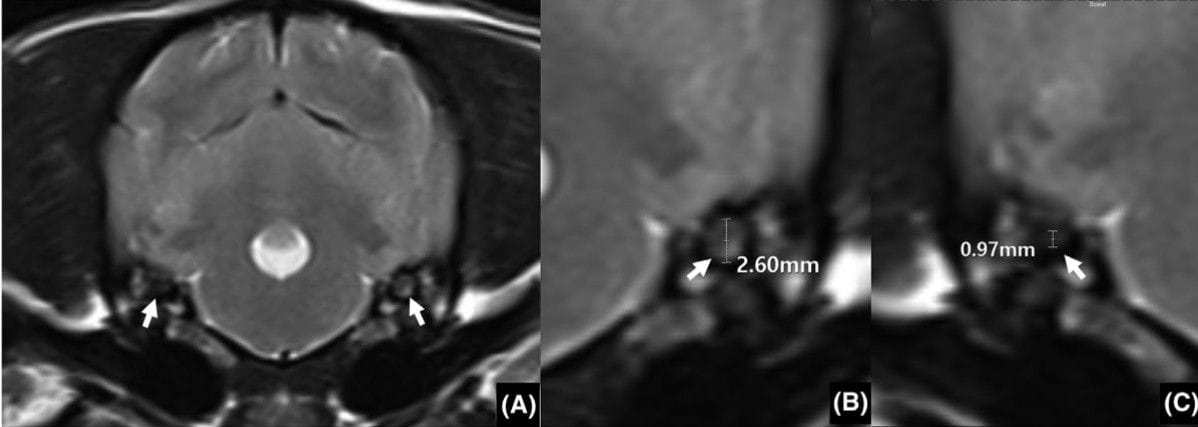

Transverse T2 weighted image of the idiopathic vestibular syndrome (IVS). The oval shape of the utricle was obviouslyasymmetrical (arrow) in the IVS patient (A). Measurement of the utricle size in the largest side (B) and smallest side (C) is indicated by a whitearrow. The utricle asymmetricity ratio (UAR) was calculated by dividing the largest to the smallest utricle diameter

Dogs with IVS showed significantly greater utricle asymmetry than control dogs (median UAR 0.83 vs. 0.98, P < 0.01). Within the IVS group, dogs whose smaller utricle correlated with the side of clinical signs (“consistent group”) had lower UARs (0.82) compared with inconsistent cases (0.90, P < 0.01). No correlation was found between UAR and age, sex, or head-tilt direction. In dogs with UAR < 0.73, utricle size reduction always matched the side of clinical signs, suggesting meaningful structural asymmetry.